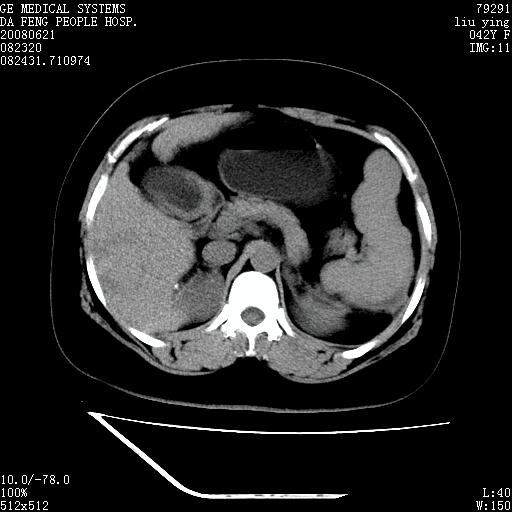

标题: CT14225:女性46岁。当地B超示肝内占位,来我院作CT检查。请 [打印本页]

标题: CT14225:女性46岁。当地B超示肝内占位,来我院作CT检查。请

速升速降,支持肝癌.脾体积增大,形态欠规整,请询问病史是否做过脾动脉栓塞.

速升速降,支持肝癌可能。

快进快出,符合肝癌表现-----------

肝内结节强化特点符合原发性肝癌表现,脾脏改变考虑为增大及先天发育所致。

动脉期病原灶明显强化高于肝密度且中央有无强化区,静脉期强化程度下降明显,延迟低于肝密度,考虑肝腺瘤可能性大,

肝内结节强化特点:快进快出符合原发性肝癌表现

此患者虽然符合快进的特点,却不符合快出的特点,因为门脉期几乎是等密度,不符合肝癌的增强表现,所以我考虑肝局灶性结节增生可能性大